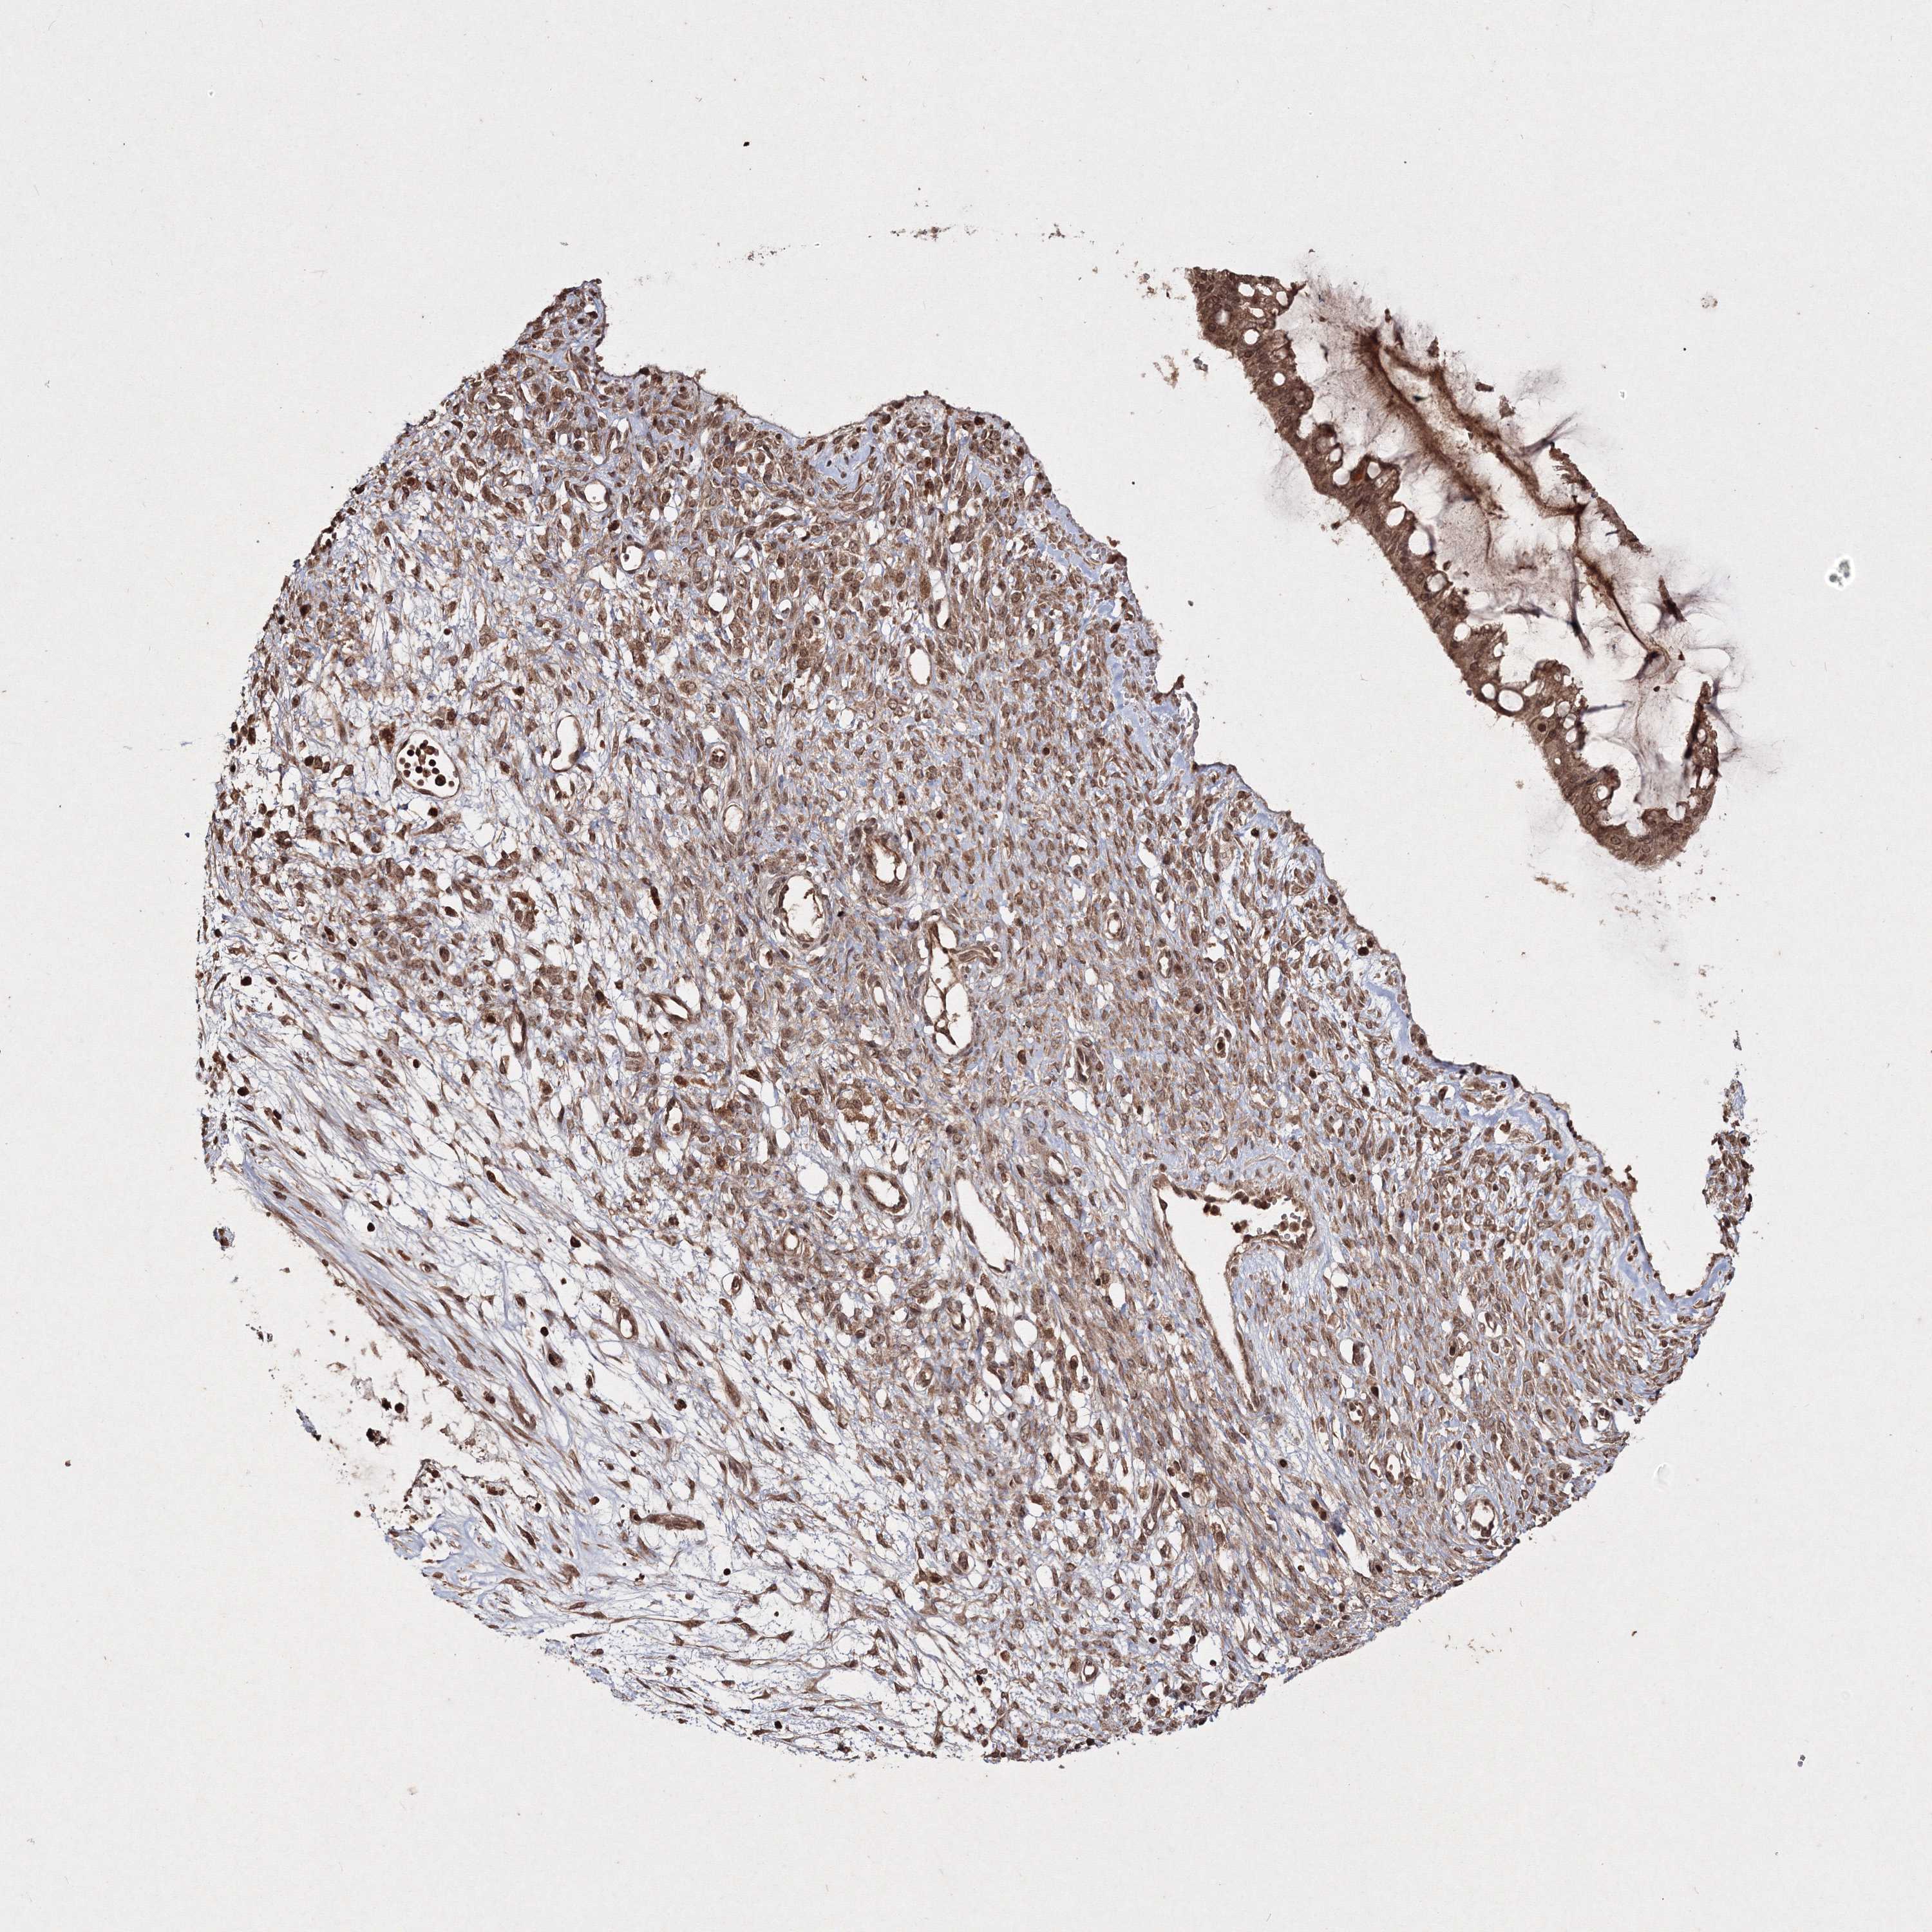

OVARIAN CANCER - Protein expressioni

A mouse-over function shows sample information and annotation data. Click on an image to view it in a full screen mode. Samples can be filtered based on level of antibody staining by selecting one or several of the following categories: high, medium, low and not detected. The assay and annotation is described here.

Note that samples used for immunohistochemistry by the Human Protein Atlas do not correspond to samples in the TCGA dataset.

Antibody stainingi

Antibody staining in the annotated cell types in the current human tissue is reported as not detected, low, medium, or high, based on conventional immunohistochemistry profiling in selected tissues. This score is based on the combination of the staining intensity and fraction of stained cells.

Each image is clickable and will lead to virtual microscopy that enables deeper exploration of all samples and also displays staining intensity scores, fraction scores and subcellular localization as well as patient and tissue information for each sample.

Antibody HPA032141

Antibody HPA032142

Antibody CAB032689

Staining

High

Medium

Low

Not detected

Intensity

Strong

Moderate

Weak

Negative

Quantity

>75%

75%-25%

<25%

None

Location

Nuclear

Cytoplasmic/membranous

Cytoplasmic/membranous,nuclear

Cystadenocarcinoma, serous, NOS

Carcinoma, endometroid

Cystadenocarcinoma, mucinous, NOS

Carcinoma, NOS